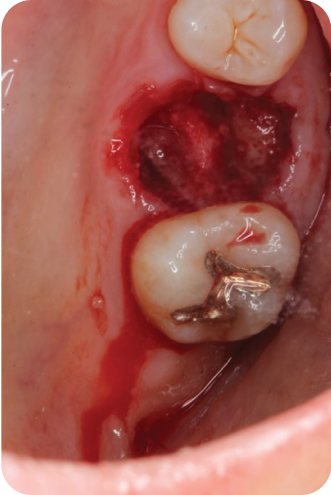

Lecture Topic

The first day will focus on pre-extraction site evaluation, dental implant planning, and site preservation procedures to ensure a smooth path towards surgical implant placement. The second day will focus on simple strategies for guided bone regeneration when there is a horizontal ridge deficiency.

Techniques for staged and simultaneous guided bone regeneration with implant placements will taught. Techniques utilising autologous bone, allografts, xenografts and alloplasts will be covered in depth.

The course will introduce the use of autologous blood concentrates such as PRF and CGF in regeneration procedures. Different membranes and their indications such as collagen and Ti-reinforced PTFE will also

be covered.

Day 2

Lecture & Hands-on

4

Post extraction site cleaning

and disinfection

and disinfection